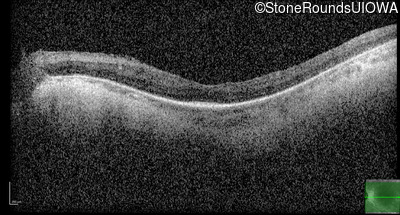

Optical Coherence Tomography - Right - 20/50 -2

Exemplar / OCT Stack